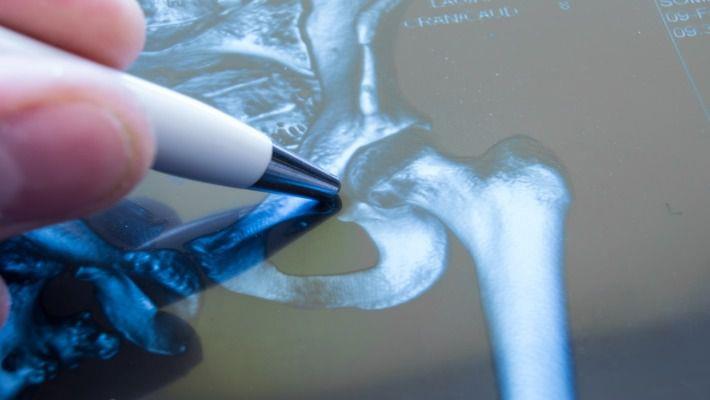

ראשית כל תתבצע בדיקה פיזיקלית על ידי אורתופד מומחה. בנוסף יתבצעו צילומים של המפרק, לרבות צילומים מיוחדים בעמידה, כדי לבחון את העומס על המפרק. במקרים מסוימים יהיה צורך בבדיקה נוספת, כמו בדיקת MRI או בדיקתCT של המפרק.מהן דרכי הטיפול בשחיקת מפרק?